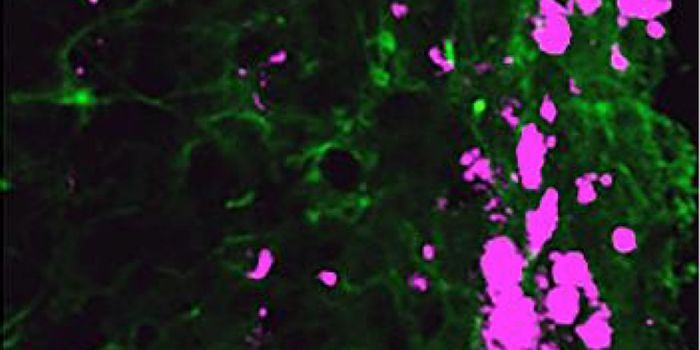

FEB 21, 2023Cell & Molecular BiologyThe Griffith Lab at UNC discovered telomeric protein & potential biomarker VR (green), shown in the nuclei (blue) of hum ...